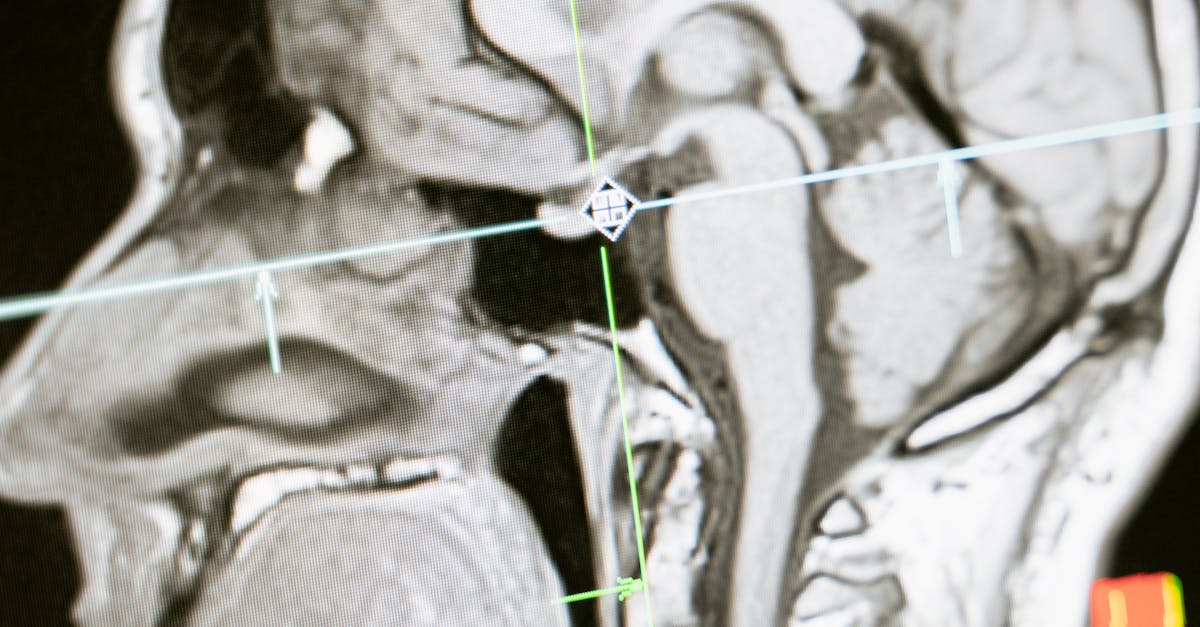

Another major advancement in radiography technology is the introduction of computed tomography (CT) scans. CT scans use a combination of X-rays and computer technology to create cross-sectional images of the body. This allows healthcare providers to obtain detailed 3D images, enabling them to diagnose and treat a variety of medical conditions more effectively. With these technological advancements, radiography has become an indispensable tool in modern medicine, providing healthcare professionals with valuable insights into the human body.

Radiography practices have evolved significantly over the years, thanks to advancements in technology. The integration of digital imaging techniques has revolutionized the way radiography is conducted, offering higher image quality, efficiency, and reduced exposure to radiation. With the introduction of digital radiography systems, traditional film-based methods are becoming obsolete, allowing for quicker image acquisition, manipulation, and sharing, ultimately expediting the diagnostic process.

Furthermore, the use of artificial intelligence (AI) in radiography practices is gaining momentum, offering automated tools for image interpretation and analysis. AI algorithms can assist radiographers in detecting abnormalities, enhancing diagnostic accuracy, and providing valuable insights for treatment planning. Moreover, technological innovations such as 3D imaging, virtual reality, and mobile X-ray units have expanded the capabilities of radiography, enabling healthcare professionals to obtain detailed images for complex cases and conduct imaging procedures at the patient's bedside.